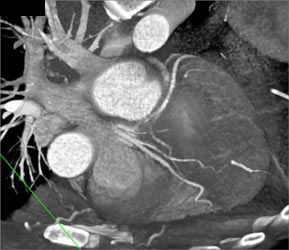

Normal RCA